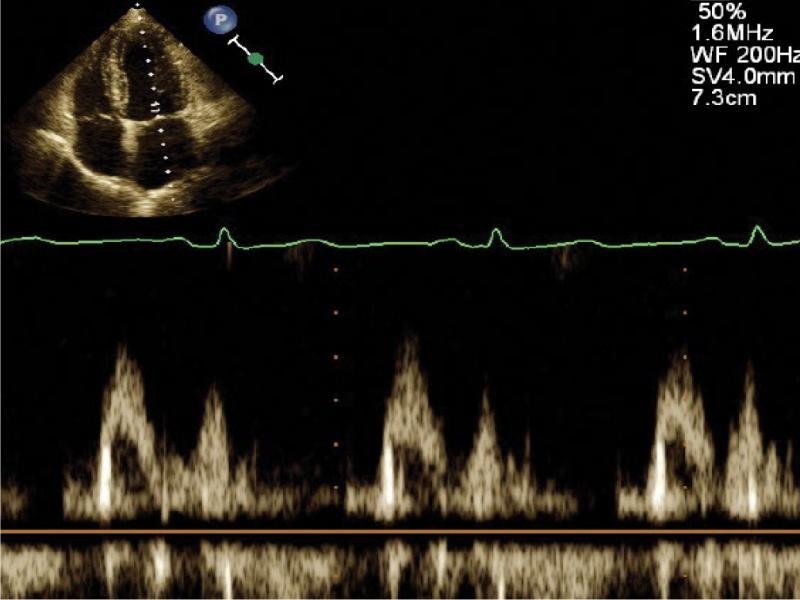

The mitral valve may be viewed in nearly any echocardiographic projection: long- and short-axis parasternal, apical 4-chamber, 2-chamber and 5-chamber. Each of these views shows different fragments of anterior and posterior leaflet, allowing for a precise assessment of the site where morphological changes occur. The short-axis parasternal view shows the cross section of the mitral valve and allows for a planimetric calculation of its area during diastole, which is estimated at 4–6 cm2 under normal conditions. The apical 4-chamber view using PWD will record mitral flow. Normal left ventricular filling pattern is biphasic (Fig. 4) with an early diastolic E wave and a late A wave. Under normal conditions, the peak left ventricular inflow velocity should not exceed 1.3 m/s.

Normal biphasic inflow into the left ventricle through the mitral valve in PWD in apical 4-chamber view